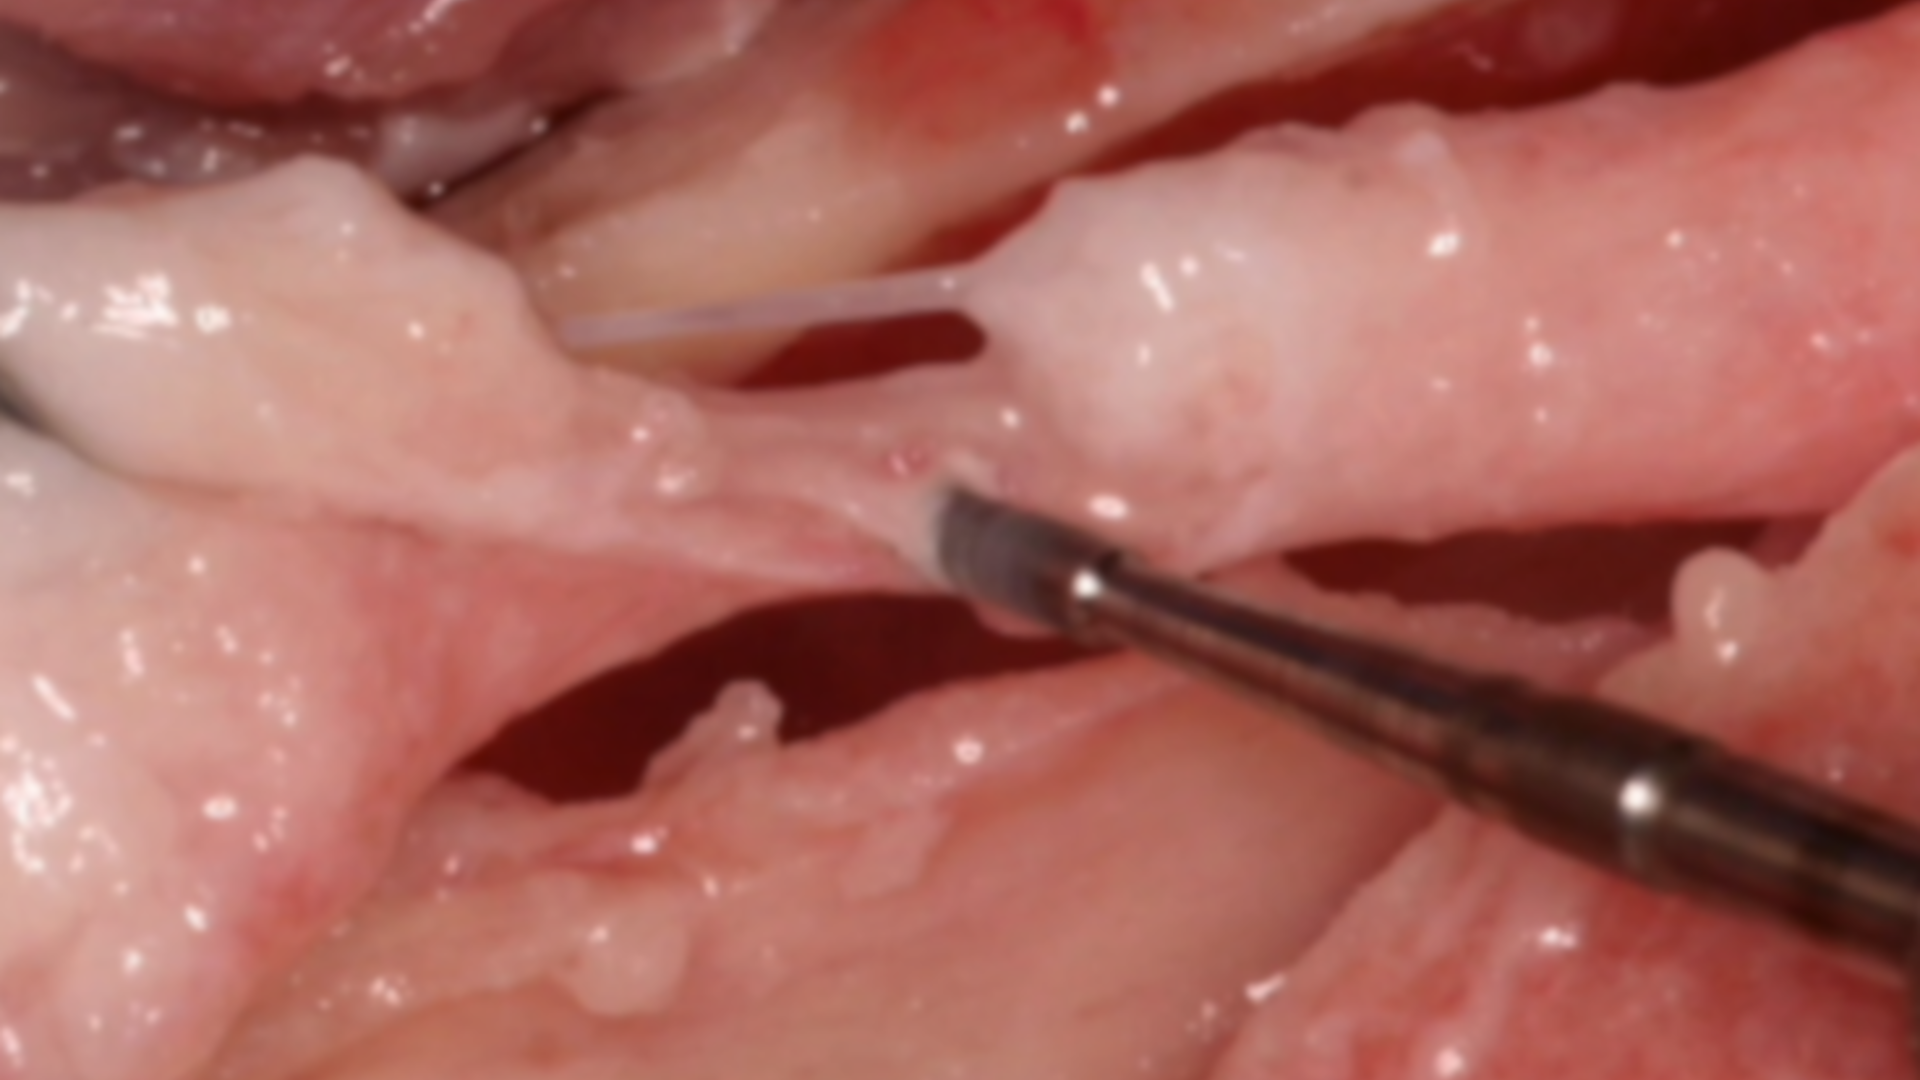

Piezoelectric approach in a partially impacted wisdom tooth extraction